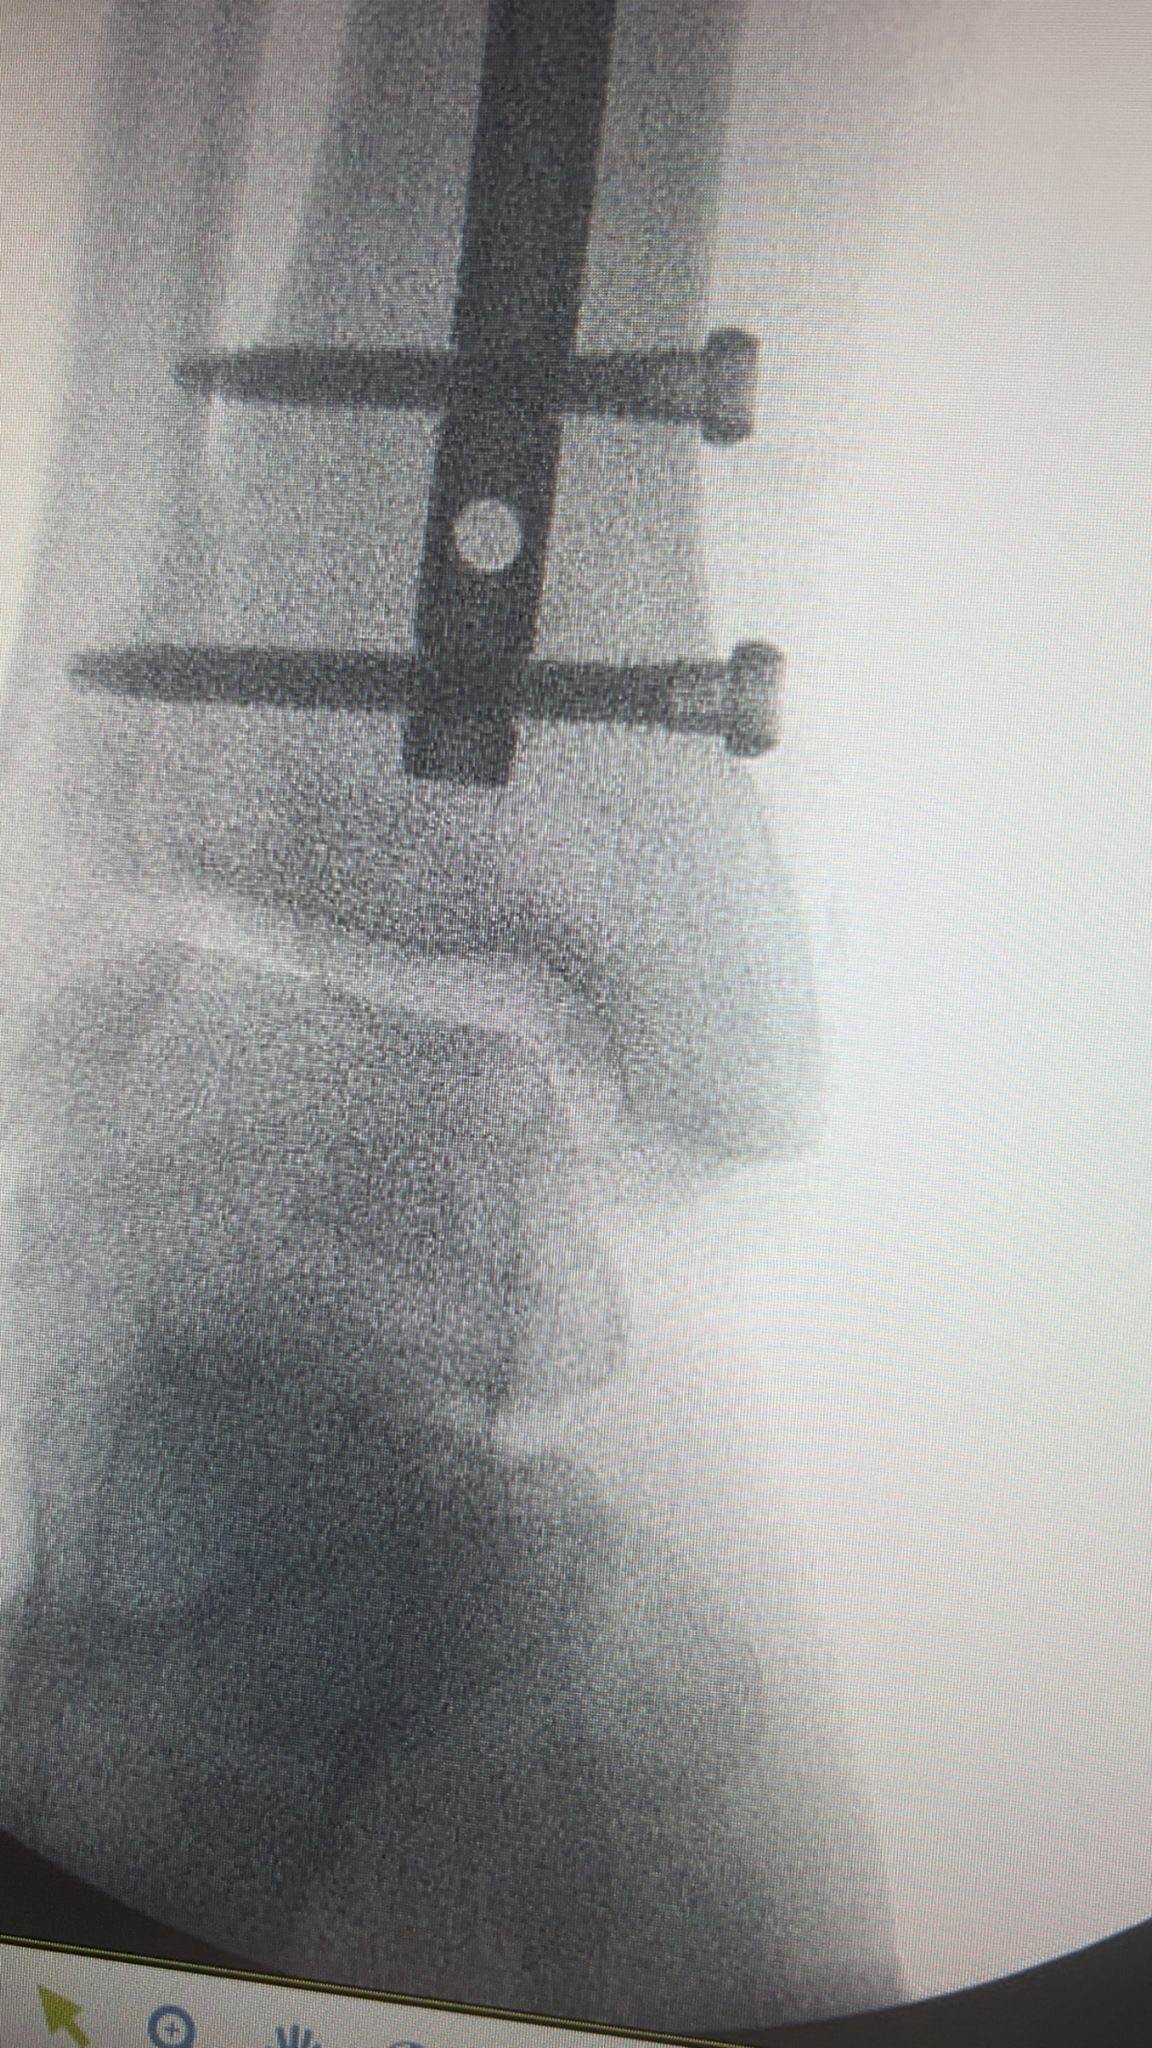

On Saturday 25th October, one of our men’s teams were playing a league match against Montpellier Reserves. During this match one of our players, Josh Swales, unfortunately suffered a triple leg fracture during a horrific tackle. The match was abandoned and Josh was rushed to hospital. In hospital Josh was put into a cast and transferred to Gloucester Royal Hospital. On Monday 27th October, Josh had surgery to insert a metal rod and 4 screws into his leg. On Thursday 30th October, Josh was discharged with crutches to continue recovery from home. He was told he would be unable to put full weight through the leg for at least 6 weeks, be off work for 8-12 weeks and out of any exercise for 4-6 months.